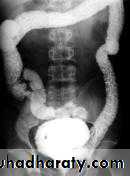

Imaging findings

o 90-95% rate of detection by BEo Polypoid filling defect

o Annular constricting >>>>> apple-core lesion